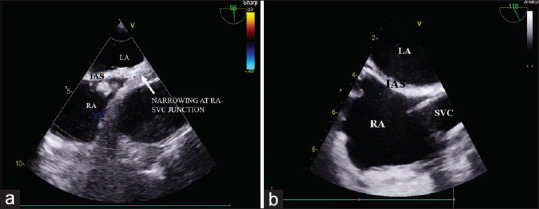

Perioperative iatrogenic superior vena cava obstruction after cardiopulmonary bypass diagnosed by combined pulmonary artery catheter and transesophageal echocardiography.

肺动脉导管联合经食管超声心动图诊断体外循环术后围手术期医源性上腔静脉梗阻。